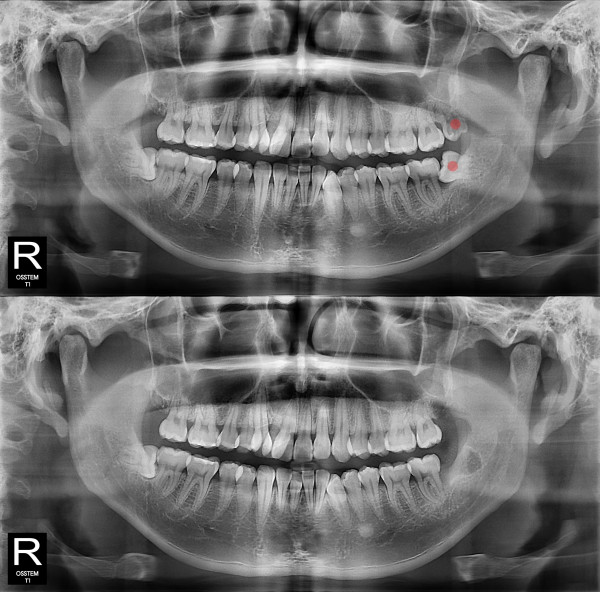

사랑니발치 부분 매복 사랑니

826e40416d712e6cd444a78bde93df4b_1767857762_7274.jpg